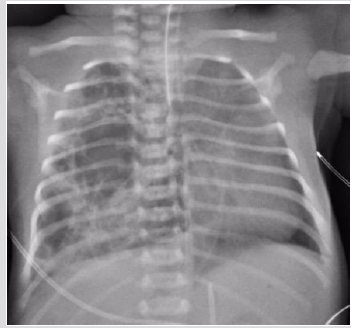

A male born at 30th week of pregnancy, of 1100-g, developed respiratory distress after delivery and chest X-ray showed the signs of a Respiratory Distress Syndrome (RDS). The baby was intubated. During the second day of life, a typical PIE was detected, on the third day of life a large retro cardiac air collection was identified. The lucency was on the midline (Figure 3). CT was performed to localize the large air collection that appeared oblong, well circumscribed, and crossing the midline. There was shift of the mediastinal structures anteriorly. The air-filled mass was interpreted either an infra-azygous pneumomediastinum or an air collection in the pulmonary ligament [5]. Over the following week, the extra ventilatory air collections is gradually resorbed: the large midline gas collection became smaller and didn’t shift laterally suggesting an infra azygous pneumomediastinum [6]. During the subsequent week, the median gas collection has shrunk but it not shifting sideways (Figure 3).

Figure 3E Chest X ray (AP View). One week later shrinking of the collection persistent on the midline arrows).